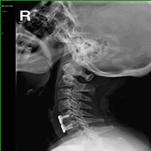

颈椎间盘突出、颈椎管狭窄——开展颈椎前路、后路手术治疗颈椎间盘突出、颈椎管狭窄,解除许多患者病痛,通过网上会诊方便患者,在家就能得到著名脊柱外科专家王少波教授诊治。

1).C4/5、C5/6间盘突出术前、 术后(C5椎体次全切除,钛笼植入)

2). C5-C6间盘突出术前、 术后(间盘切除,Cage植入)